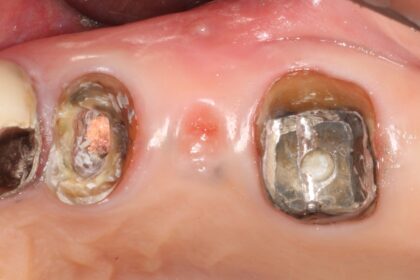

症例4

| 項目 | 詳細 |

|---|---|

| 患者様データ | 60代 女性 |

| 来院時の主訴 | 「残りの人生を健康的に噛めるようになりたい。」 |

| 医院の診断 |

虫歯の再発、歯周病を併発した慢性根尖性歯周炎 |

| 通院期間 | 1年間 |

| 来院回数 | 8回 |

| 治療費 | 480,000円(税抜) 《内訳》 精密感染根管治療100,000円、ファイバーポストコア20,000円、セラミック治療120,000円×3 |

| リスクと副作用 | ①根管治療歯は長期的には破折するリスク ②メインテナンスが必要 |

| ココがこだわりのポイント☝ |

ラバーダム防湿とマイクロスコープを使用して丁寧に治療を行いました。 再根管治療のため、殺菌性があり歯を補強することのできる根管充填材料を使用しています。 歯周病を併発していましたが、患者様の日々の歯磨きの努力により、改善することができました。 |